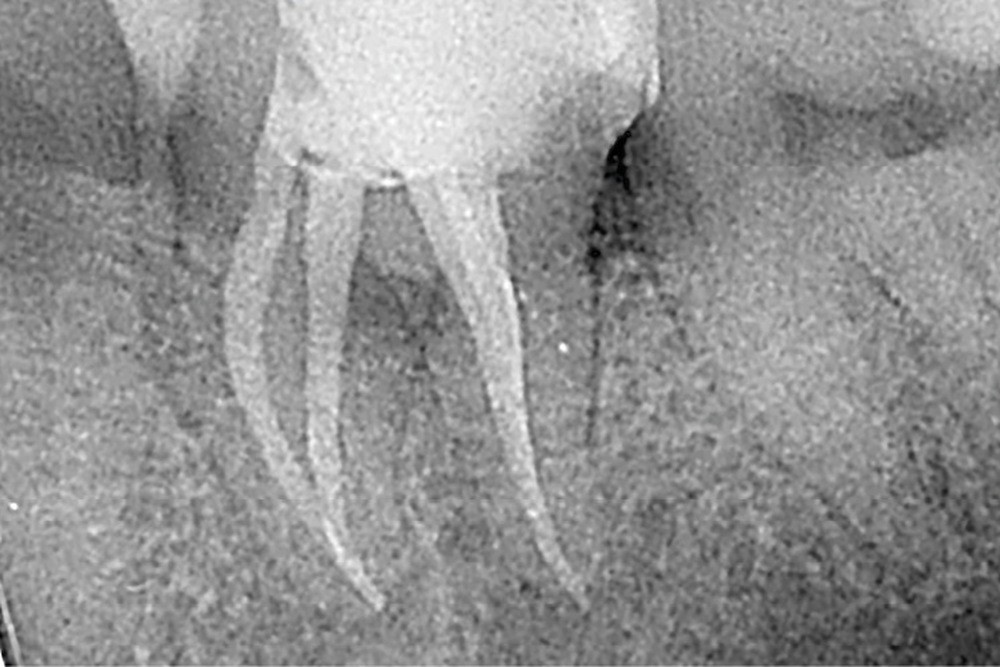

La mise en forme doit également s’adapter aux singularités anatomiques. Pour ce cas clinique, le canal mésio-lingual a été mis en forme en premier jusqu’à la longueur de travail. Puis le test du cône a été réalisé (fig. 4 et 5) afin de voir si les deux canaux se rejoignaient. Ces deux canaux se rejoignant à 3 mm de l’apex, le canal mésio-vestibulaire a été mis en forme à sa longueur de travail moins 3 mm afin d’éviter la zone de confluence et le risque accru de fracturer un instrument. De plus, cette mise en forme longueur de travail-3 mm a son importance pour la précision de l’obturation et l’ajustage des cônes. Pour le canal distal, qui était un canal « en 8 », nous appliquons le même raisonnement que pour les canaux mésiaux, avec un canal principal, test du cône, et ajustage des maîtres-cônes (fig. 6).

Un rinçage à l’hypochlorite de sodium 3 % est réalisé entre chaque passage d’instrument. Enfin, nous faisons un rinçage final avec une activation sonique, à l’EDTA 17 % (phase minérale), puis à l’hypochlorite de sodium 3 % (phase organique). Le séchage avant l’obturation est réalisé avec une micro-aspiration et des cônes de papier calibrés.